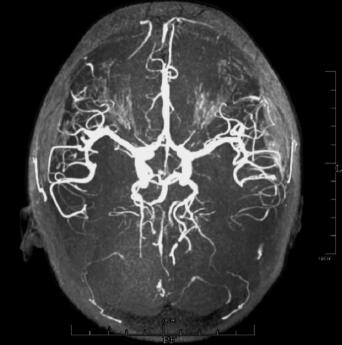

影像学检查:2011年4月26日行颅脑MRI(发病后5天)示:左侧颞、额、顶叶交界区及左侧额叶大脑镰旁可见不规则脑回状稍长T1稍长T2信号,沿皮质分布;DWI序列和FLAIR序列示左侧颞、顶叶交界区的斑片状高信号影(图1),余脑实质内未见明显异常信号区。提示左侧额、颞、顶叶异常信号,首先考虑急性脑梗死。2011年4月27日行MRA:右侧大脑后动脉起自颈内动脉,余大血管分布及形态基本正常(图2)。

图2 2011年4月27日行头颅MRA检查,右侧大脑后动脉起自颈内动脉,未见颅内血管狭窄、硬化等异常征象